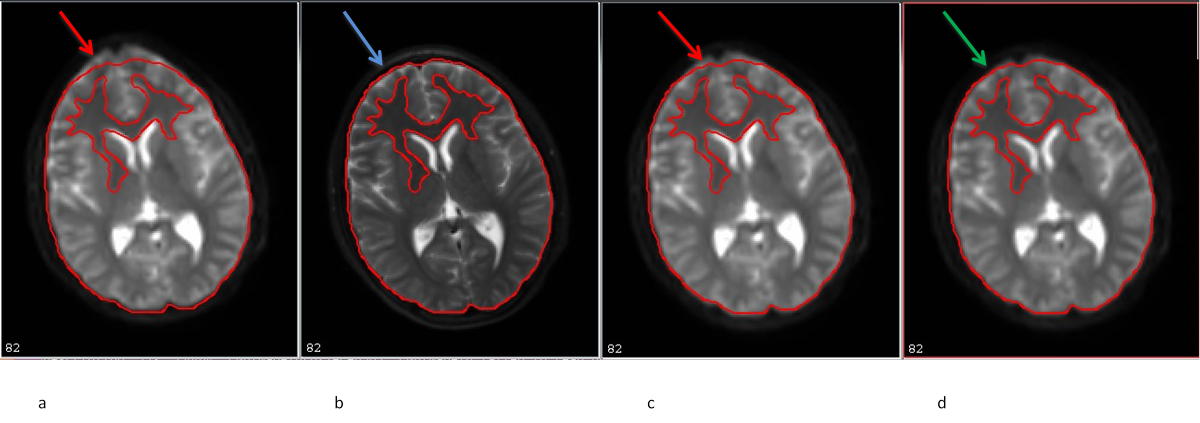

11.9. DEC map output including and excluding the corrupt volume

Note: The arrows, inserted by author, points to the artifactual and corrected regions that are clearly seen on the DEC map.

- Left: DEC map of data with the corrupt volume. Red arrow shows the residual uncorrected data points.

- Right: DEC map of data after the corrupt volume is removed. Green arrow shows a cleaner map.